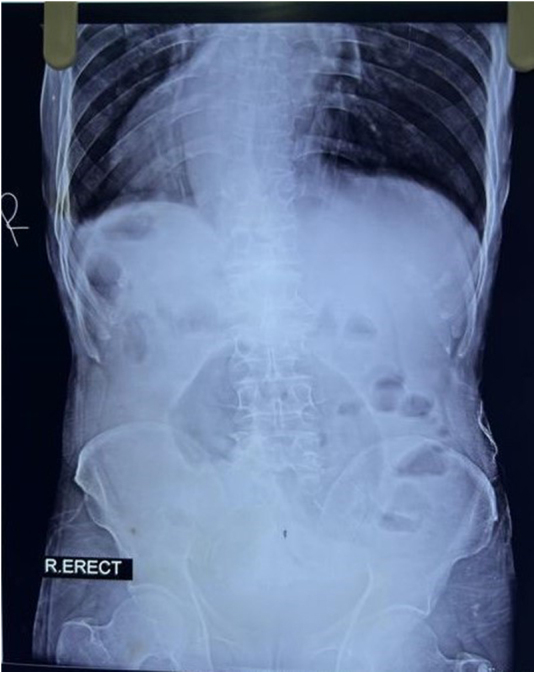

Case presentation: A 76-year-old male presented with abdominal pain and obstipation for 5 days. Clinical examination and imaging revealed signs of bowel obstruction and dextrocardia. Computed tomography (CT) scan abdomen confirmed sigmoid volvulus and situs inversus totalis. Emergency laparotomy revealed a 360-degree twisted, dilated sigmoid colon. Manual detorsion and excision of fibrous bands were performed. The patient recovered uneventfully.